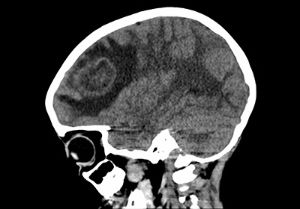

Above, a patient receives a full workup at the New Onset Seizure Clinic.

Through this program, children can receive evaluation and treatment earlier after experiencing their first seizure.